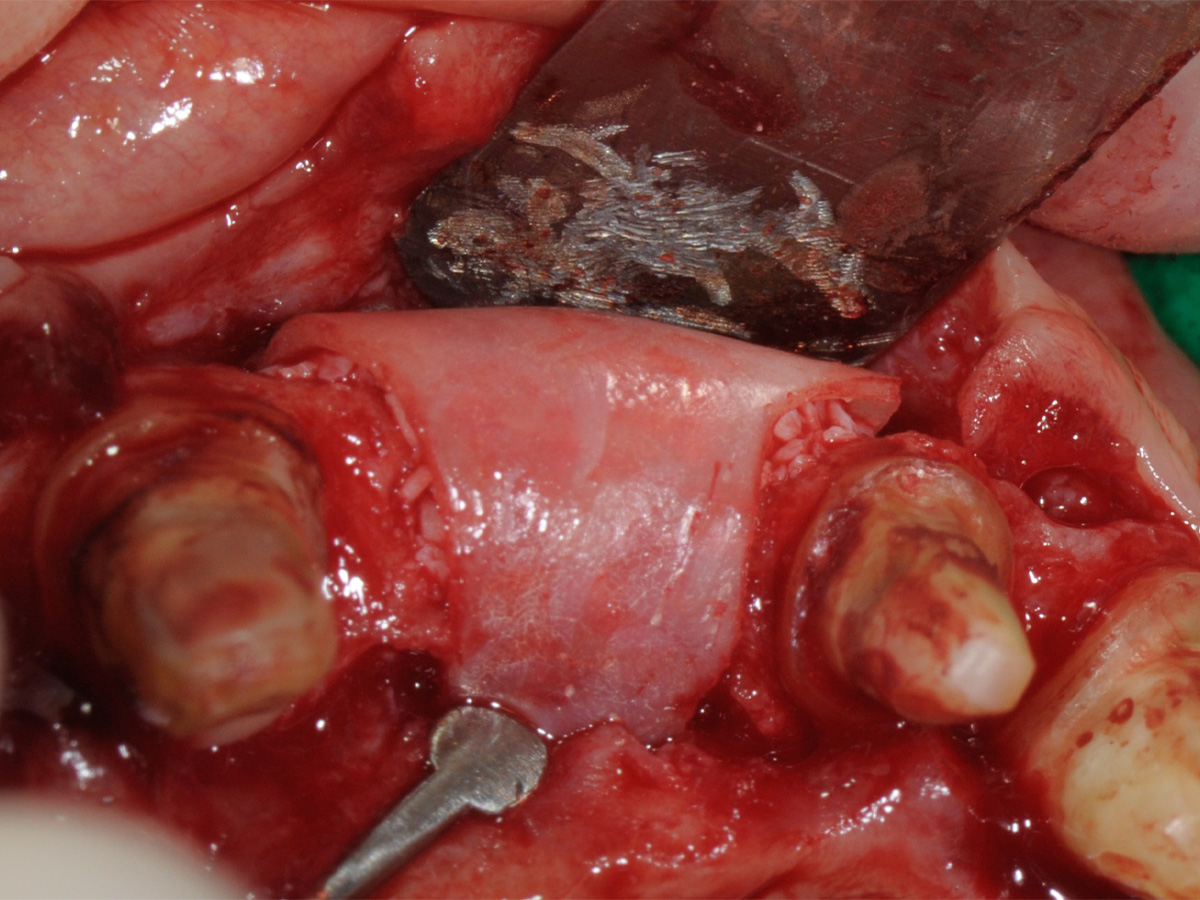

Abbildung 6

Dargestellter Defekt.

Abbildung 7

Abbildung 8

Aufbau mit OsteoBiol® mp3, Bone Lamina Soft und Evolution.